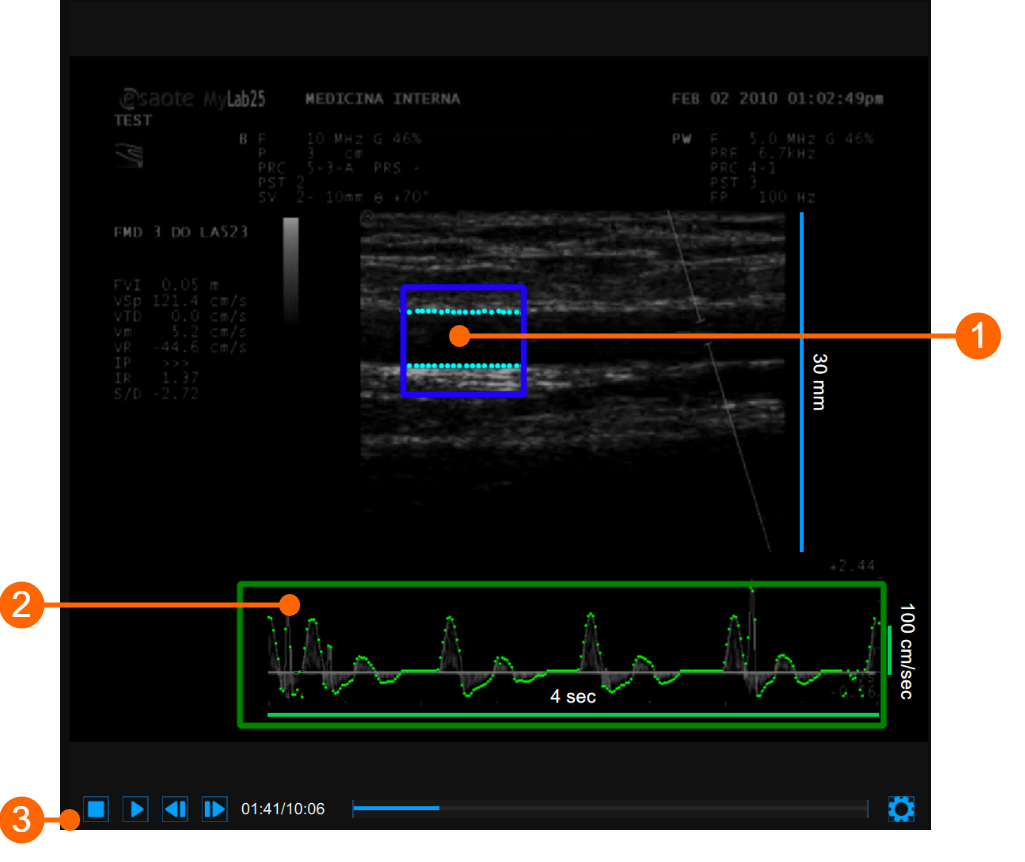

The video window shows the video signal from your ultrasound system. Two ROIs can be present in the window: the diameter ROI in blue (1) and the Doppler flow ROI in green (2).

The Video control bar (3) is located at the bottom of the window.